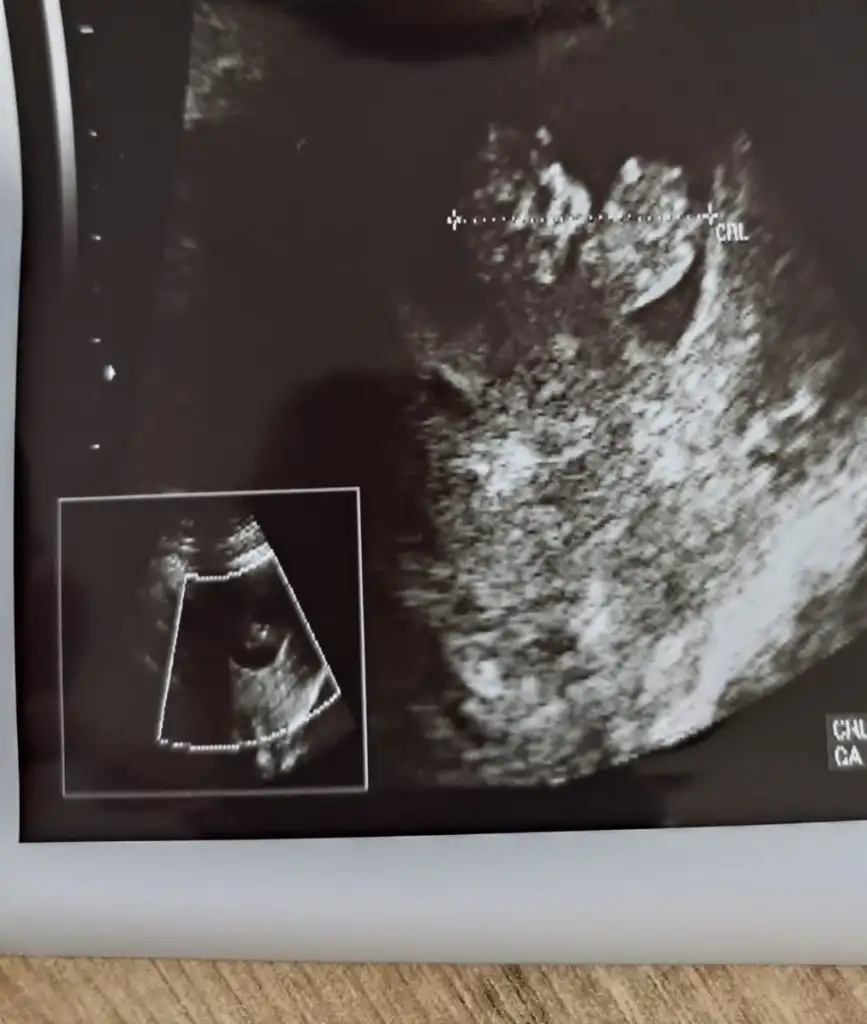

Erkek bence :)Allah rizasi icin 12 +4 yorum yapabilirmisiniz

Bebeğin yonu ne tarafa bakıyor eger assagi dogru ise erkek derim ama yukari dogru bakıo sa kiz. Anlayamadım durusunu kafasina gore yukarı bakıyor sankiAllah rizasi icin 12 +4 yorum yapabilirmisiniz

Kız gibi duruyor bence kız olcakKizlar bana da bakar msnzzz

Erkek cnm nubu dikMerhaba kızlar üstte gördünüz resmî yorumlayabilirmisiniz çok merak ediyorum cinsiyetini